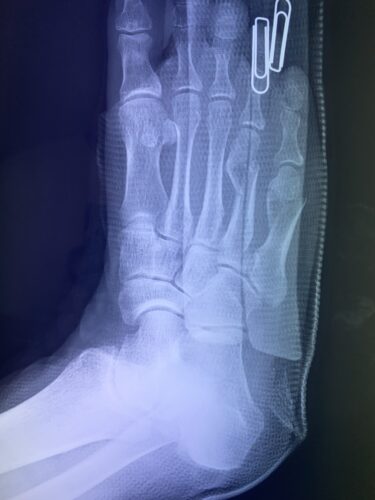

第5中足骨骨折の1症例について